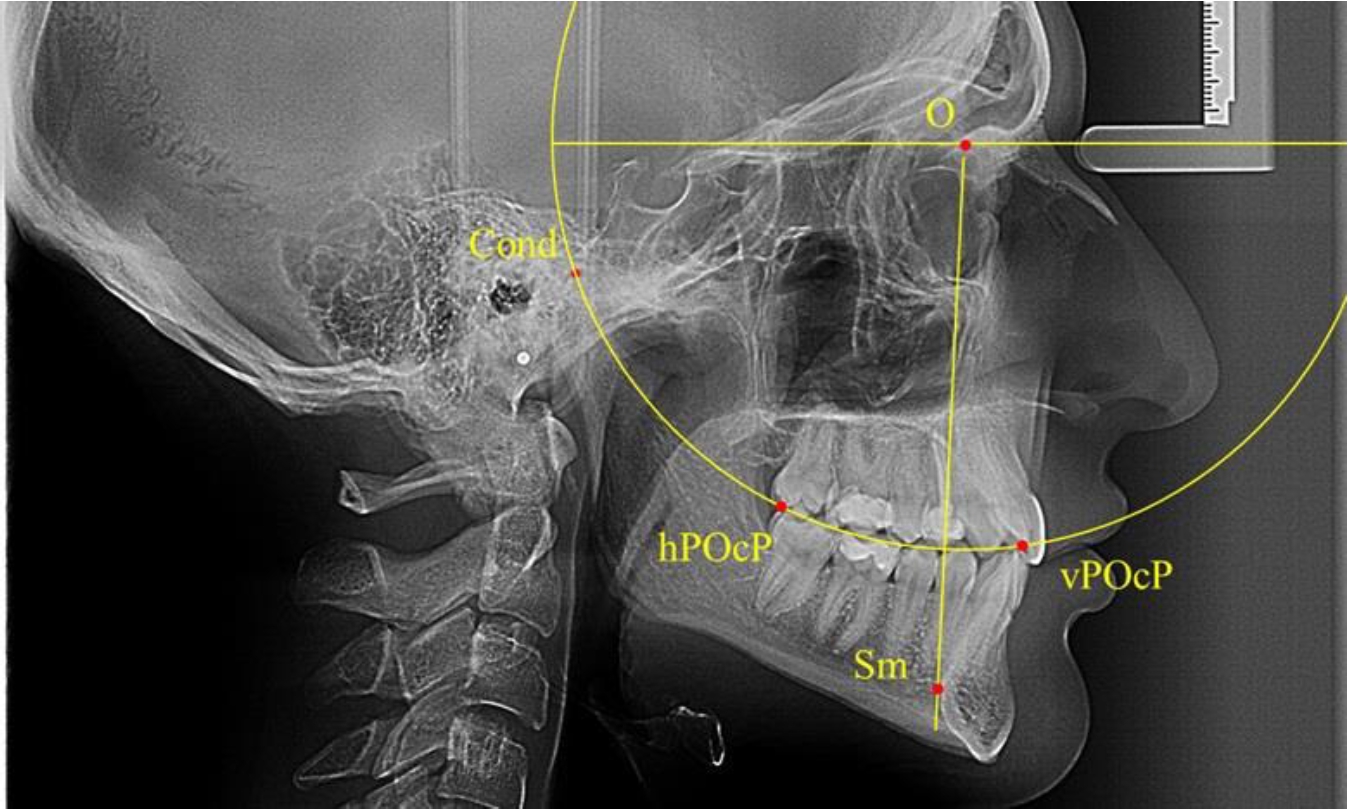

В группе рентгенограмм с ретрузионным положением резцов также проводилось распределение на подгруппы с учетом широтных размеров подбородочного выступа.

Анализ результатов показал, что практически при всех вариантах подбородочного выступа в данной группе исследования первые премоляры, как правило, располагались либо на стресс-оси Bimler, либо позади. Рентгенограммы пациентов с ретрузионным положением резцов при широком и среднем варианте подбородочного выступа представлены на рис. 4.

Таким образом, для людей с ретрузионным типом зубочелюстных дуг характерно расположение первых премоляров позади стресс-оси либо на средней линии, и этот показатель не может быть использован в качестве выбора метода лечения аномалий для данной группы исследования вне зависимости от формы подбородочного выступа.

Рис. 4. Положение первых верхних премоляров при ретрузии с широкими (а) и средними (б) размерами подбородка